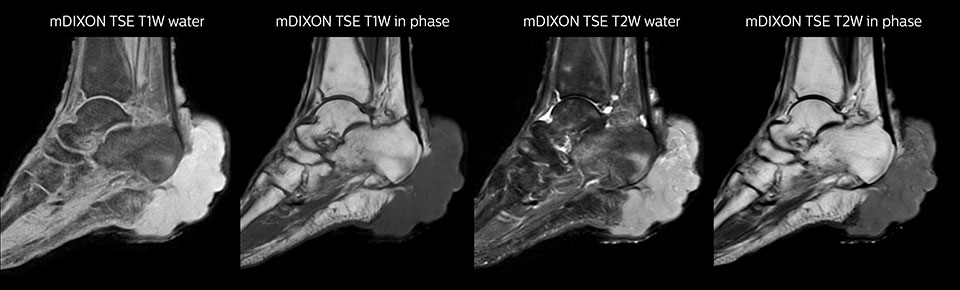

mDIXON TSE of ankle

MRI examination on Prodiva 1.5T of a 72-year-old female with a malignant melanoma in the ankle. mDIXON TSE provides excellent fat

suppression, without the distortion that is often seen at such extremities.

mDIXON TSE of ankle melanoma